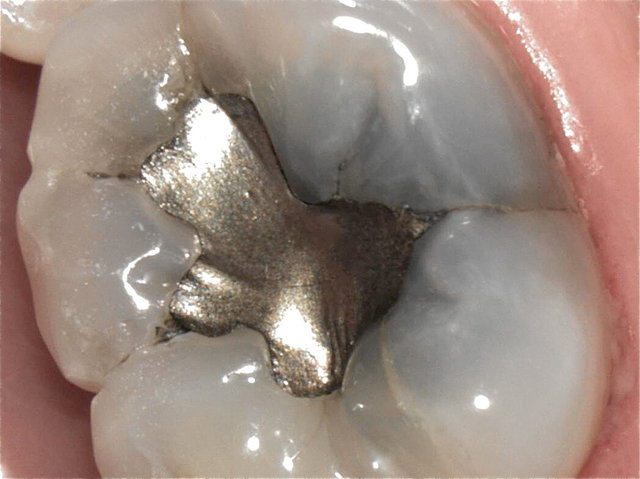

Alte Amalgam-Füllungen mit Sekundärkaries ...

Composit-Füllungen by CLINICDENT ✓